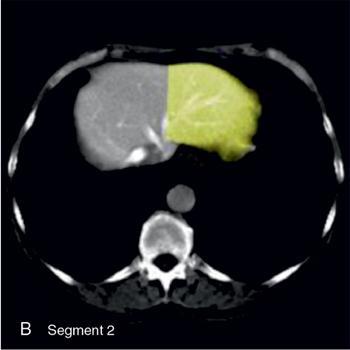

Ritu K. Kashikar, Shrinivas B. Desai Imaging is the mainstay of noninvasive diagnosis of the spectrum of abdominal pathologies or proving absence off thereof. Knowledge of normal anatomy and important normal variants is thus essential for the radiologist in order to avoid misinterpretation or erroneous diagnosis. This chapter highlights the normal anatomy of the hepatobiliary systems including the blood vessel and draining ducts and discusses relevant anatomical variants which may have important clinic implications. The liver is the largest abdominal organ, occupying the right upper abdominal quadrant and is in close approximation with the diaphragm, stomach and the gallbladder. It is largely covered by the costal cartilages. The liver is encapsulated by Glisson’s capsule which is a dense layer of connective tissue. It is covered by peritoneum, except in the regions of gallbladder fossa, fossa for inferior vena cava (IVC), and the bare area. The bare area is the posterocranial aspect of the liver, adjacent to the dorsal body wall, which is not covered by peritoneum. The liver has two surfaces, the convex diaphragmatic surface and a concave visceral surface. The slit in the hepatic hilum is called the porta hepatis and is penetrated by the right and left hepatic ducts (LHDs), hepatic artery and portal vein (PV). The distal portion of the lesser omentum is called the hepatoduodenal ligament and contains the common bile duct (CBD), hepatic artery, PV, nerves of liver and lymphatics. The liver has dual blood supply with hepatic artery providing 25% of hepatic blood and rest by portal vein (Fig. 9.2.1). Five ligaments connect the liver to the undersurface of the diaphragm. These include the falciform, the coronary and two lateral ligaments, all of which are peritoneal folds. The fifth ligament is a fibrous cord-like structure and represents the obliterated umbilical vein. The peritoneum invaginates into the liver parenchyma leading to formation of fissures. There are four normal fissures: fissures for the ligamentum teres, ligamentum venosum and gallbladder and the transverse fissure (Fig. 9.2.2). The liver is organized into microscopic functional units called lobules or acini. A central terminal hepatic venule surrounded by four to six terminal portal triads form a polygonal unit called the hepatic lobule. The terminal portal triad branches line the periphery of the unit. Between the terminal portal triads and the central hepatic venule the hepatocytes are arranged in one cell thick plates, surrounded by sinusoids. The blood flows from the terminal portal triad through sinusoids into terminal hepatic venule. Bile formed within the hepatocytes empties into terminal canaliculi which coalesce into the bile ducts (Fig. 9.2.3). This structure of the functional hepatic unit forms the basis of various functions of the liver. The normal relations of the liver are: The liver can be divided into right, left and caudate lobes. The right and left lobes are separated by the interlobular fissure and is oriented along a line passing through the gallbladder fossa inferiorly and the middle hepatic vein (MHV) superiorly (Fig. 9.2.4). This plane runs from the left of the IVC to the left of the gallbladder fossa and is a called the Cantlie’s line. Use of standardized, segmental anatomy is imperative because it facilitates communication and treatment planning. The segmental anatomy of liver is primarily based on vascular anatomy. The right lobe is divided into anterior and posterior sectors by of the right hepatic vein (RHV). The left lobe is divided into medial and lateraI sectors by an oblique plane connecting the left hepatic vein (LHV) and the falciform ligament. The liver is divided into upper and lower segments at the level of main portal vein (MPV) bifurcation (Fig. 9.2.5). Various systems are used in classification of liver anatomy. These are discussed in Table 9.2.1. The Couinaud’s system is the most commonly used and divides eight sections/segments which are discussed in details below (Table 9.2.2). 1. Segment 1 – Caudate lobe Bounded anteriorly and medially by the fissure for ligamentum venosum (Fig. 9.2.6). 2. Segment 2: Superior segment of the left lateral sector/section Bounded medially by falciform ligament and inferiorly by plane of MPV, also known as the posterior lateral sector (Bismuth, FCAT) (Fig. 9.2.7). 3. Segment 3: Inferior segment of left lateral sector/section Bounded medially by the falciform ligament and superiorly by the plane of the MPV bifurcation, also referred to as lateral anterior sector (Bismuth, FCAT) (Fig. 9.2.8). 4. Segment 4: Left medial sector/section Bounded laterally by falciform ligament and medially by Cantlie’s line (Fig. 9.2.9). 5. Segment 5: Inferior segment of the right anterior sector/section Bounded anteriorly by the gallbladder fossa and posteriorly by the plane of the RHV, superiorly bounded by the plane of MPV bifurcation (Fig. 9.2.10). 6. Segment 6: Inferior segment of the right posterior sector/section Bounded anteriorly by plane of the RHP and superiorly by the plane of the MPV bifurcation (Fig. 9.2.11). 7. Segment 7: Superior segment of the right posterior sector/section Bounded anteriorly by the plane of the RHV and inferiorly by the plane of the MPV bifurcation (Fig. 9.2.12). 8. Segment 8: Superior segment of the right anterior sector/section Bounded anteriorly by the plane of the gallbladder fossa and MHV, posteriorly bounded by the plane of the RHV and inferiorly by the plane of the MPV bifurcation (Fig. 9.2.13). Owing to its broad area of contact with the anterior abdominal wall, the liver is an ideal organ for evaluation with sonography. Ultrasound is commonly used for evaluation of size of the liver. On longitudinal scans obtained through the midhepatic line, if the liver measures 13 cm or less, it is normal in 93% of individuals (Fig. 9.2.14). The size of liver in various planes is discussed in chapter on normograms. When the area of contact between the liver and the anterior border of the right kidney, exceeds below two thirds of the kidney, the liver is considered as enlarged. The normal liver is homogeneous with fine echoes and appears evenly bright. The hepatic veins, PV and fissures interrupt the homogeneity of the liver parenchyma (Fig. 9.2.15). The parenchymal echogenicity may vary depending on the equipment, transducer and gain settings and should be judged by comparison with internal references like right renal cortex, body of the pancreas and PV walls. When compared with the adjacent normal right renal cortex the liver normally appears hyperechoic or isoechoic. The pancreas in a young individual is hypoechoic compared to the liver, and isoechoic in middle aged adults. As age progresses and fatty infiltration of the pancreas occurs, the pancreas appears hyperechoic to the liver. The liver is hypoechoic to the spleen. The normal liver reveals a density of 55–65 HU on nonenhanced scan and should appear homogenous with the exception of hypodensity in the regions of vessels and fissures. The liver parenchymal enhancement is minimal the arterial phase, with increase in density by only approximately 10 HU. This phase is usually to access vascular anatomy and to detect neovascular enhancing lesion like HCC, metastasis. Considering the fact that 75% of heptic venous supply is from the PV, the normal hepatic parenchyma shows maximum enhancement in the portal venous phase. During the venous/delayed phase the hepatic attenuation starts falling (Fig. 9.2.16). The hepatic fissures appear as linear fat containing structures. All the four fissures are well identifies on CT (Figs. 9.2.17–9.2.20). Normal liver should demonstrate uniform T1 signal similar or isointense to the paraspinal muscles and slightly hyper intense to the spleen. No signal drop should be seen on in or opposite phase. On T2W1 images liver appears slightly hyperintense to paraspinal muscles, isointense to pancreas and hypointense to spleen (Fig. 9.2.21). Following administration of extracellular contrast agents the normal liver parenchyma enhances on PV phase similar to that seen on CT. The arterial phase is preserved to determining vascular anatomy, variants and tumoural enhancement. Gadoxetic acid (Eovist) and gadobenate dimeglumine (MultiHance) are hepatobiliary agents showing excretion by the liver. In the case of gadoxetic acid, hepatic excretion is ~50%, which allows imaging in the hepatobiliary phase at ~20 minutes following injection. Gadobenate has only 3%–5% biliary excretion with hepatobiliary phase at approximately 40 minutes (Fig. 9.2.22). This property makes these agents useful in detection of nonhepatocyte containing lesions which appear hypointense to background liver on hepatobiliary phase. Hepatic anatomic variants are relatively common and represent normal interindividual variation of liver morphology. Normal Anatomic Variants Anatomic anomalies Accessory and pseudofissures may be seen in the liver. True accessory fissures result from infolding of the peritoneum usually along the undersurface of the liver and are rare. The inferior accessory fissure is the commonest accessory fissure and divides the posterior segment of the right hepatic lobe into lateral and medial portions. Diaphragmatic slips may cause indentation over the liver surface and are not commonly seen on imaging (Fig. 9.2.23). Leftward extension of the lateral segment of the left hepatic lobe appearing as a crescentic density that wraps around the spleen is referred to as sliver of liver. The left lobe of the liver may exhibit various forms: leaf like; spatular; truncated pyramid/wedge shaped; and a bifid appearance (Fig. 9.2.24). Elongated left lobe may be mimic splenomegaly, perisplenic hypoechoic collections or less commonly tumours. Imaging clues to diagnosis are establishing contiguity with liver and visualization of parenchymal vessels coursing through. The portion of the liver that extends medially from the right lobe between the IVC and fissure for ligamentum venosum is called the caudate lobe. The caudate lobe is divided inferiorly into a lateral caudate process and a medial papillary process. The medial papillary process projects medially towards the pancreatic head and has applied importance (Fig. 9.2.25). Riedel’s lobe is a tongue-like projection from the anterior aspect of the right lobe and the most common accessory lobe of the liver. It is seen most frequently in asthenic women. The reported prevalence of RL, ranges from 3.3% to 14.5% and the prevalence is higher in women than in men. It can be 20 cm or more in length and may extend up to the iliac fossa. It is usually asymptomatic and is discovered incidentally (Fig. 9.2.26). Accessory liver lobes are defined as a supernumerary lobe of normal hepatic parenchyma in continuity with the liver. This is a rare entity and usually occurs as a result of congenital ectopic hepatic tissue, although rarely may occur as a result of trauma or surgery. Various systems are proposed for classification of ALL. Another method of classification has been proposed based on biliary drainage and presence or absence of capsule. Accessory lobes can be readily diagnosed and characterized on CT or magnetic resonance imaging (MRI) done for related or unrelated conditions. CT shows the lesion as a soft–tissue density mass attached to the liver and isodense to the organ. The portal/hepatic venous branches can be seen coursing through it, in contiguity with the liver (Fig. 9.2.27). The coeliac axis trifurcates into common hepatic, splenic and left gastric arteries at the level of T12–L1. The common hepatic artery becomes the proper hepatic artery after origin of the gastro-duodenal artery. The hepatic artery proper ascends anterior to the PV and medial to the CBD and divides in to right and left hepatic artery (LHA). Occasionally the middle hepatic (segment 4) artery arises from hepatic artery proper. The hepatic artery appears as a tubular hypoechoic structure and shows antegrade flow on Doppler (Fig. 9.2.28). Normally the resistive index is low ranging between 0.55 and 0.7. The hepatic artery, its anatomy, branches, course, calibre are best evaluated on arterial phase of dynamic CT (Fig. 9.2.29). This is also the preferred modality prior to hepatobiliary surgical planning. Contrast-enhanced MRI also shows the above details but spatial resolution is lower. Road map of the arterial vascularity of the donor and recipient is a prerequisite for transplant surgery and complex hepatobiliary surgery. Detailed hepatic arterial anatomy and its variations have its significance in liver surgeries and interventional hepatic procedures, relative to the hepatic lobe involved. A classification method was described by Michel et al. in 1955, and is discussed in Table 9.2.3 (Fig. 9.2.30). I: standard anatomy ~60% (range 55%–61%) II: replaced LHA ∼7.5% (range 3%–10%) III: replaced RHA ~10% (range 8%–11 %) IV: replaced RHA and LHA ~1% V: accessory LHA from LGA ~10% (range 8%–11%) VI: accessory RHA from SMA ~5% (range 1.5%–7%) VII: accessory RHA and LHA ~1% VIII: accessory RHA and LHA and replaced LHA or RHA ~2.5% IX: CHA replaced to SMA ~3% (range 2%–4.5%) X: CHA replaced to LGA ~0.5% Other unclassified variants are: The two most common variants are the replaced right hepatic artery (RHA) arising from the SMA (Fig. 9.2.31) and replaced LHA arising from the left gastric artery (Figs. 9.2.32–9.2.34). Segment 4 artery – Middle hepatic artery (MHA) The middle hepatic artery usually arises from the LHA, it may, however, arise from the RHA (Fig. 9.2.35). The knowledge regarding origin of MHA is imperative in transplant surgery. The MHA can arise from RHA in Patients with replaced LHA. In patients with replaced RHA, the MHA arises from LHA (Fig. 9.2.36). Because of the considerable variability of hepatic arterial anatomy, assessment of this anatomy is crucial in the preoperative evaluation of potential living liver donors. Relevance of donor and recipient arterial anatomy is discussed in details in chapter on liver transplant. The relationship between the arterial variant and tumour is important to establish prior to major surgeries. Injuries to aberrant hepatic vessels and secondary ischaemic biliary strictures can be avoided. A replaced RHA has a more posterior course and long length. This variant may be advantageous in patients undergoing right lobar resection. However, there is greater propensity of involvement of replaced RHA by pancreatic head. The radiologist must be vigilant in reporting this variant (Fig. 9.2.37). Accessory RHA can, however, be sacrificed even if encased by neoplasm. An accessory LHA needs to be ligated separately in surgeries where blood supply in the porta hepatis is occluded. Replaced LHA from LGA maybe injured in case of surgeries at the level of hiatus. Hence this variant should be informed to surgeon in patients undergoing gastric surgeries. Preoperative mapping of the hepatic arterial anatomy prior to placement of intraarterial chemotherapy pumps is essential because it helps in deciding whether the candidate is suitable for the procedure and also if technical modifications are needed. The intraarterial infusion pump should be placed in the dominant hepatic artery as proximal as possible, but beyond GDA origin. Inpatients with standard anatomy, the pump is usually placed in the hepatic artery prior just after GDA origin. The location of pump can be modified in patients with variant anatomy, based on origin of GDA and dominant hepatic vessel. The PV is the main vessel in the portal venous system and drains blood from the gastrointestinal tract and spleen to the liver.